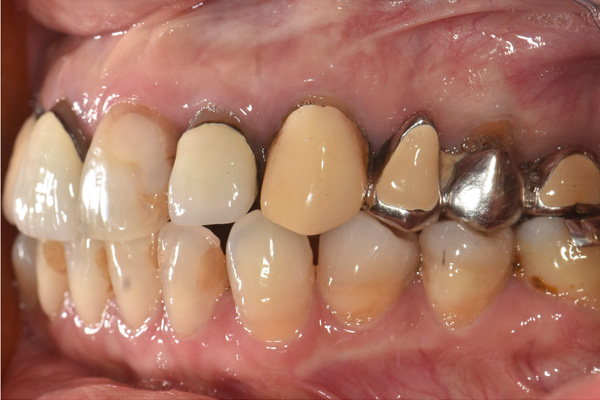

| 年代・性別 | 50代 男性 |

|---|---|

| 主訴 | 前医で前歯を抜かなければならないがインプラントはできないと言われた |

| 治療期間 | 約12ヶ月 |

| 費用 | 600,000円 |

| 治療内容 | インプラント、骨造成、結合組織移植、セラミック修復 |

| 治療に伴うリスク | インプラント周囲炎 セラミックの破折、脱離 |